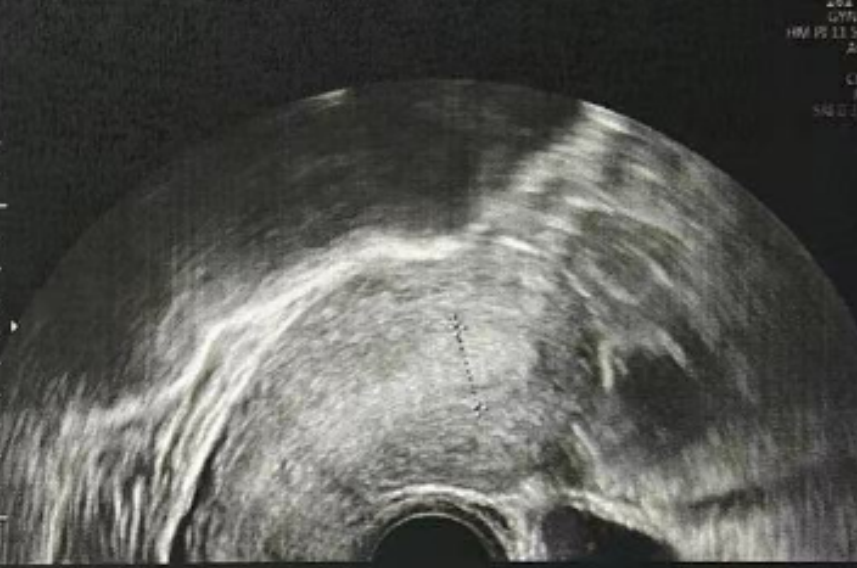

雌二醇:210.52 pg/mL

孕酮:0.3 ng/ml

子宫内膜厚度:8.9 毫米

微创清积液

在进行3毫升的子宫峡部切口冲洗后,经过经腹超声检查显示子宫内膜呈三线状,且子宫腔内未见液体。

术后给予抗生素预防感染,为后续胚胎移植扫清子宫环境障碍。